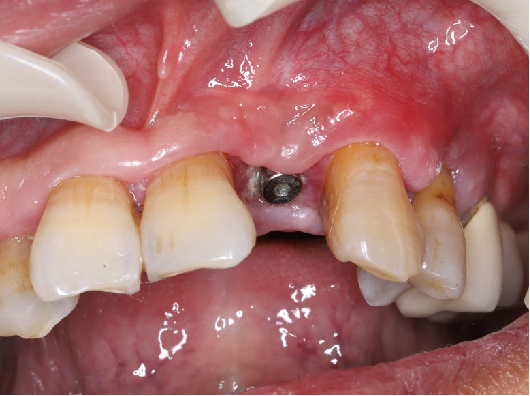

口内检查:全口牙龈轻度吸收,牙列不齐,12、22反合,口腔卫生一般。

主诉牙情况:22牙体颜色稍变暗,  松动 III 度,叩诊(-),牙 龈无红肿、溢脓、牙周袋 6mm,近远中龈乳头缺损。

术前CBCT

21颊侧牙槽骨吸收至根尖,腭侧牙槽骨吸收至根尖1/3,根周可见低密度影。牙槽嵴宽度6.41mm。

局部反合、患牙长期牙周病变,骨质缺损,但软组织无明显缺失,为II类拔牙窝形态。

22冠状位CBCT情况

唇舌牙槽嵴宽度6.41mm,垂直骨缺失1/2,软组织无垂直向缺失。